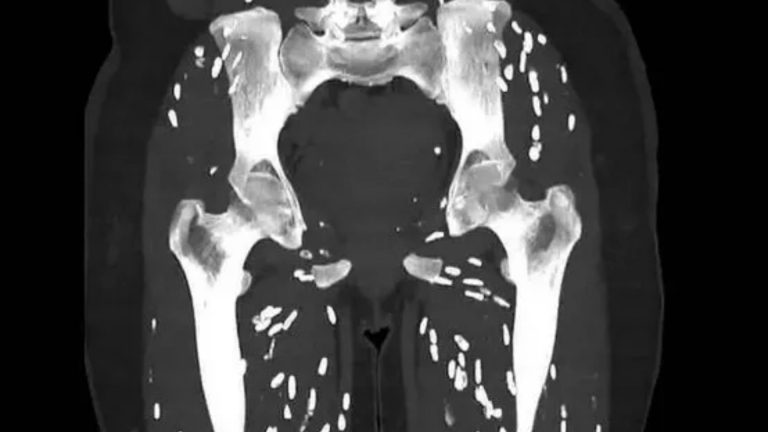

It shows the lower body of a patient, which is riddled with rice grain-like pinpricks – a telltale sign of a nasty parasitic infection that can spread to the brain, eyes or muscles.

The body’s immune system typically kills offthe cysts, which calcify and form “rice grain”-like nodules that are visible in the scan.